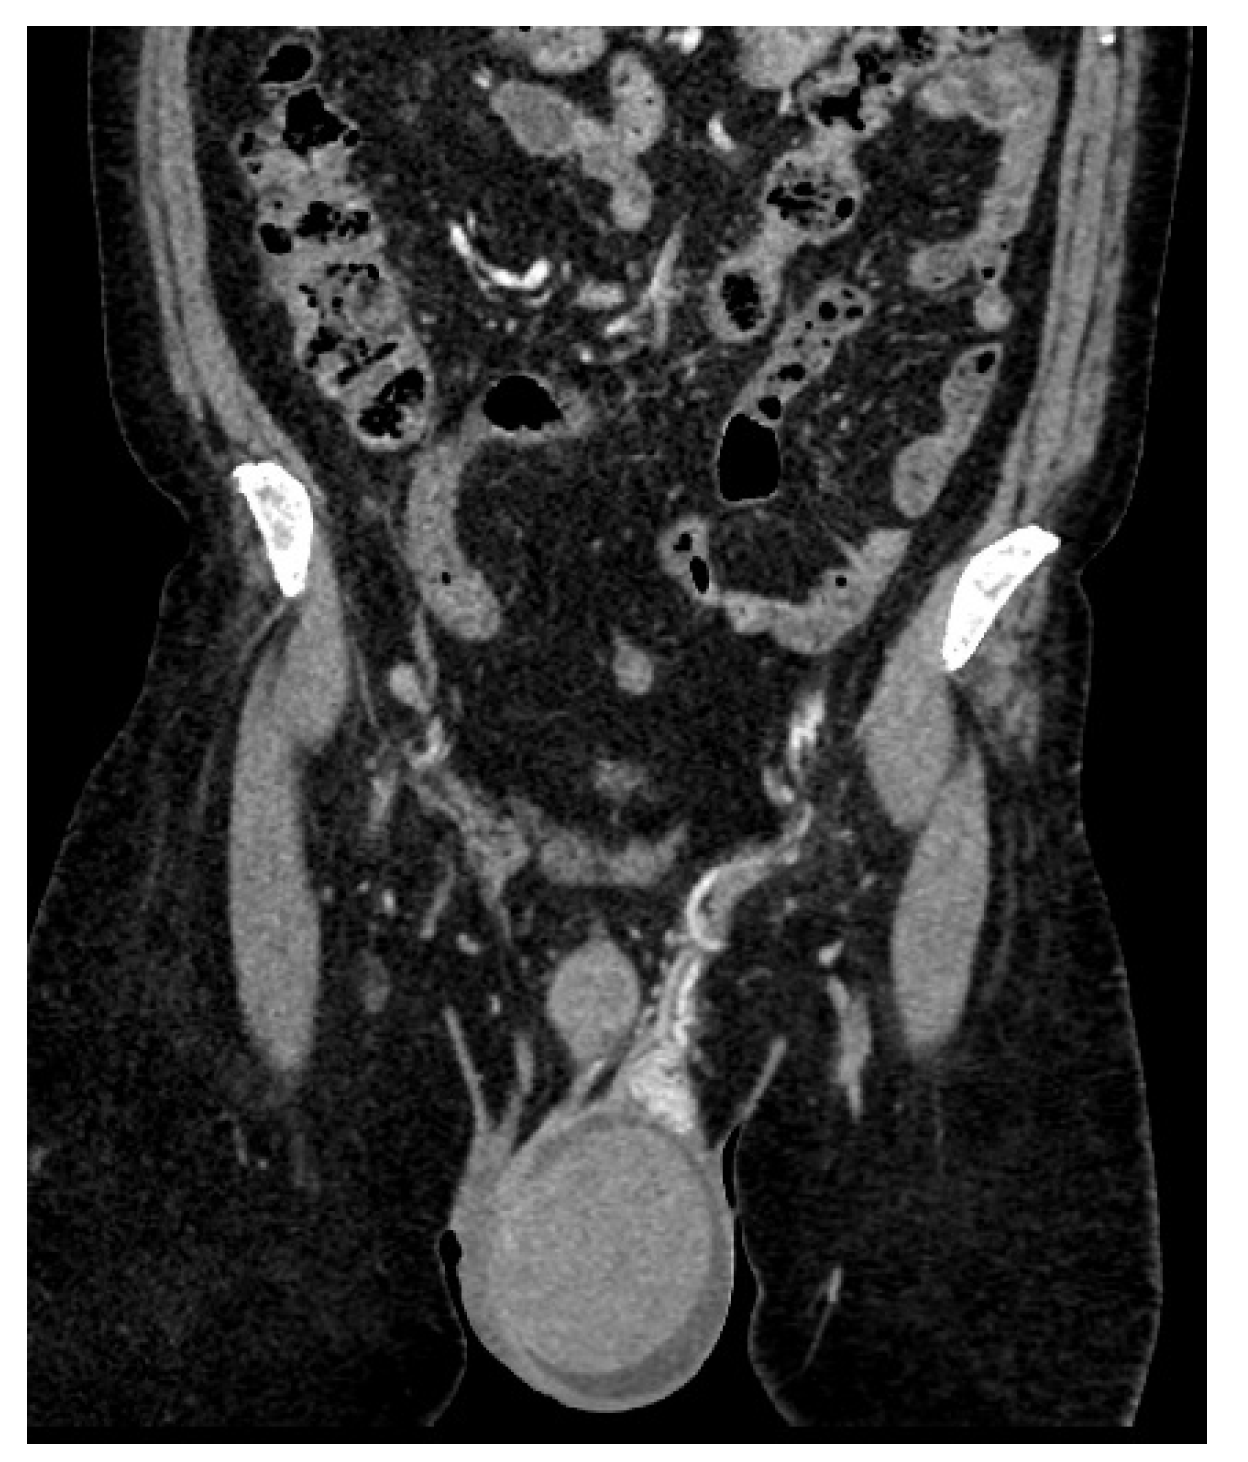

| January 2023 | second extramedullary relapse bilateral ocular left eye clinically, imaging, and biopsy demonstrated right eye demonstrated by imaging | methotrexate, asparaginase, calcium folinate radiotherapy, 30 gy/15 sessions result: imaging complete remission |

| 2 May 2023 | third emr: cardiac and colonic mass (+cns?) | nelarabine+cyclophosphamide+ etoposide |